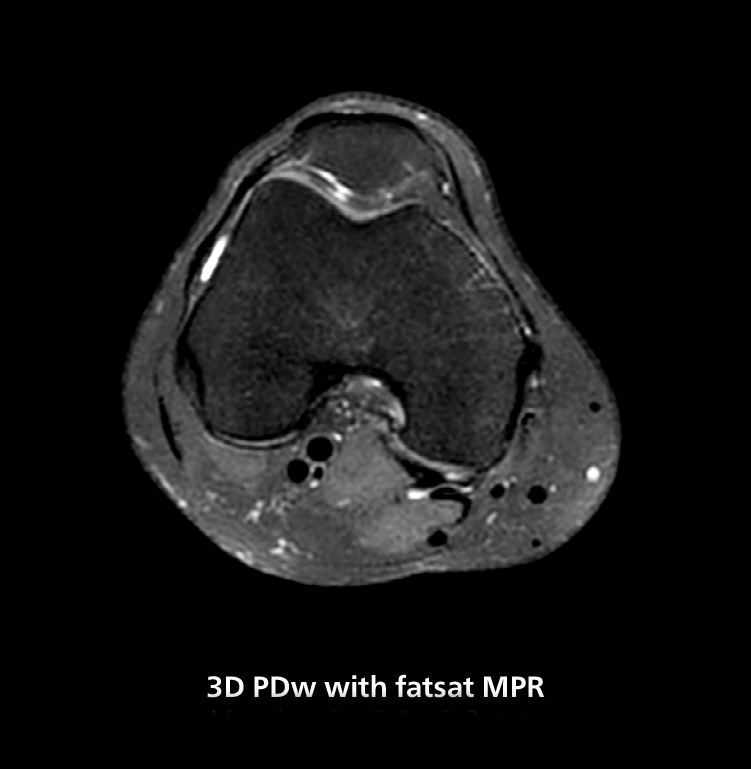

3D knee imaging

The isotropic high resolution 3D sequence in this MRI case allows for reformatting to obtain other orientations with high quality. Acquired on the MR 5300 system.

According to Dr. Gellée, the hospital conducts an average of four studies each hour, totaling about 40-45 patients per day on their MR 5300. Studies are read by approximately 50 radiologists in the Bordeaux area. Dr. Gellée is especially satisfied with the image quality of the MR system. "I obtain higher image contrast and more anatomical precision than I was used to,” she says. “When I am able to choose, I request that studies be done on this system, because I get better anatomical image quality. For example, in the knees, I can get great images of the meniscus. To me, it looks as pretty as 3T.”